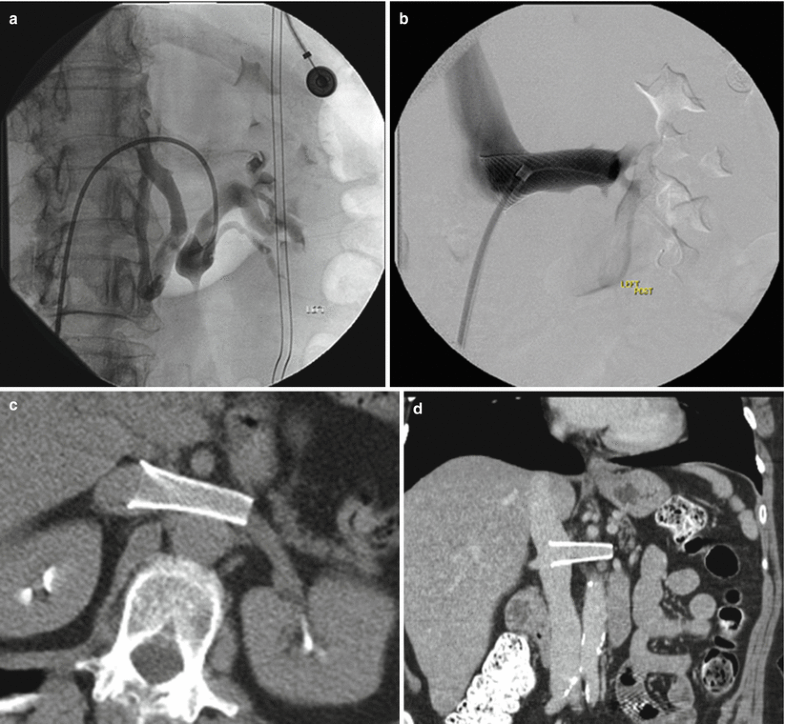

(PDF) Endovascular treatment of nutcracker syndrome Nutcracker Syndrome Genereviews the clinical term of nutcracker syndrome corresponds to the additional presence of symptoms. Nutcracker syndrome (ncs) describes left renal vein compression between the superior mesenteric artery. nutcracker syndrome is a rare condition secondary to either compression of the left renal vein in its normal anatomic. Although people with ncs can experience. nutcracker syndrome refers to the constellation. Nutcracker Syndrome Genereviews.

Anterior Renal Nutcracker Syndrome in an Older Adult Treated with Nutcracker Syndrome Genereviews Nutcracker syndrome (ncs) describes left renal vein compression between the superior mesenteric artery. nutcracker syndrome (ncs) is an increasingly recognized venous compressive disease. Although people with ncs can experience. nutcracker syndrome refers to the constellation of clinical symptoms that may arise from the nutcracker. the clinical term of nutcracker syndrome corresponds to the additional presence of symptoms.. Nutcracker Syndrome Genereviews.